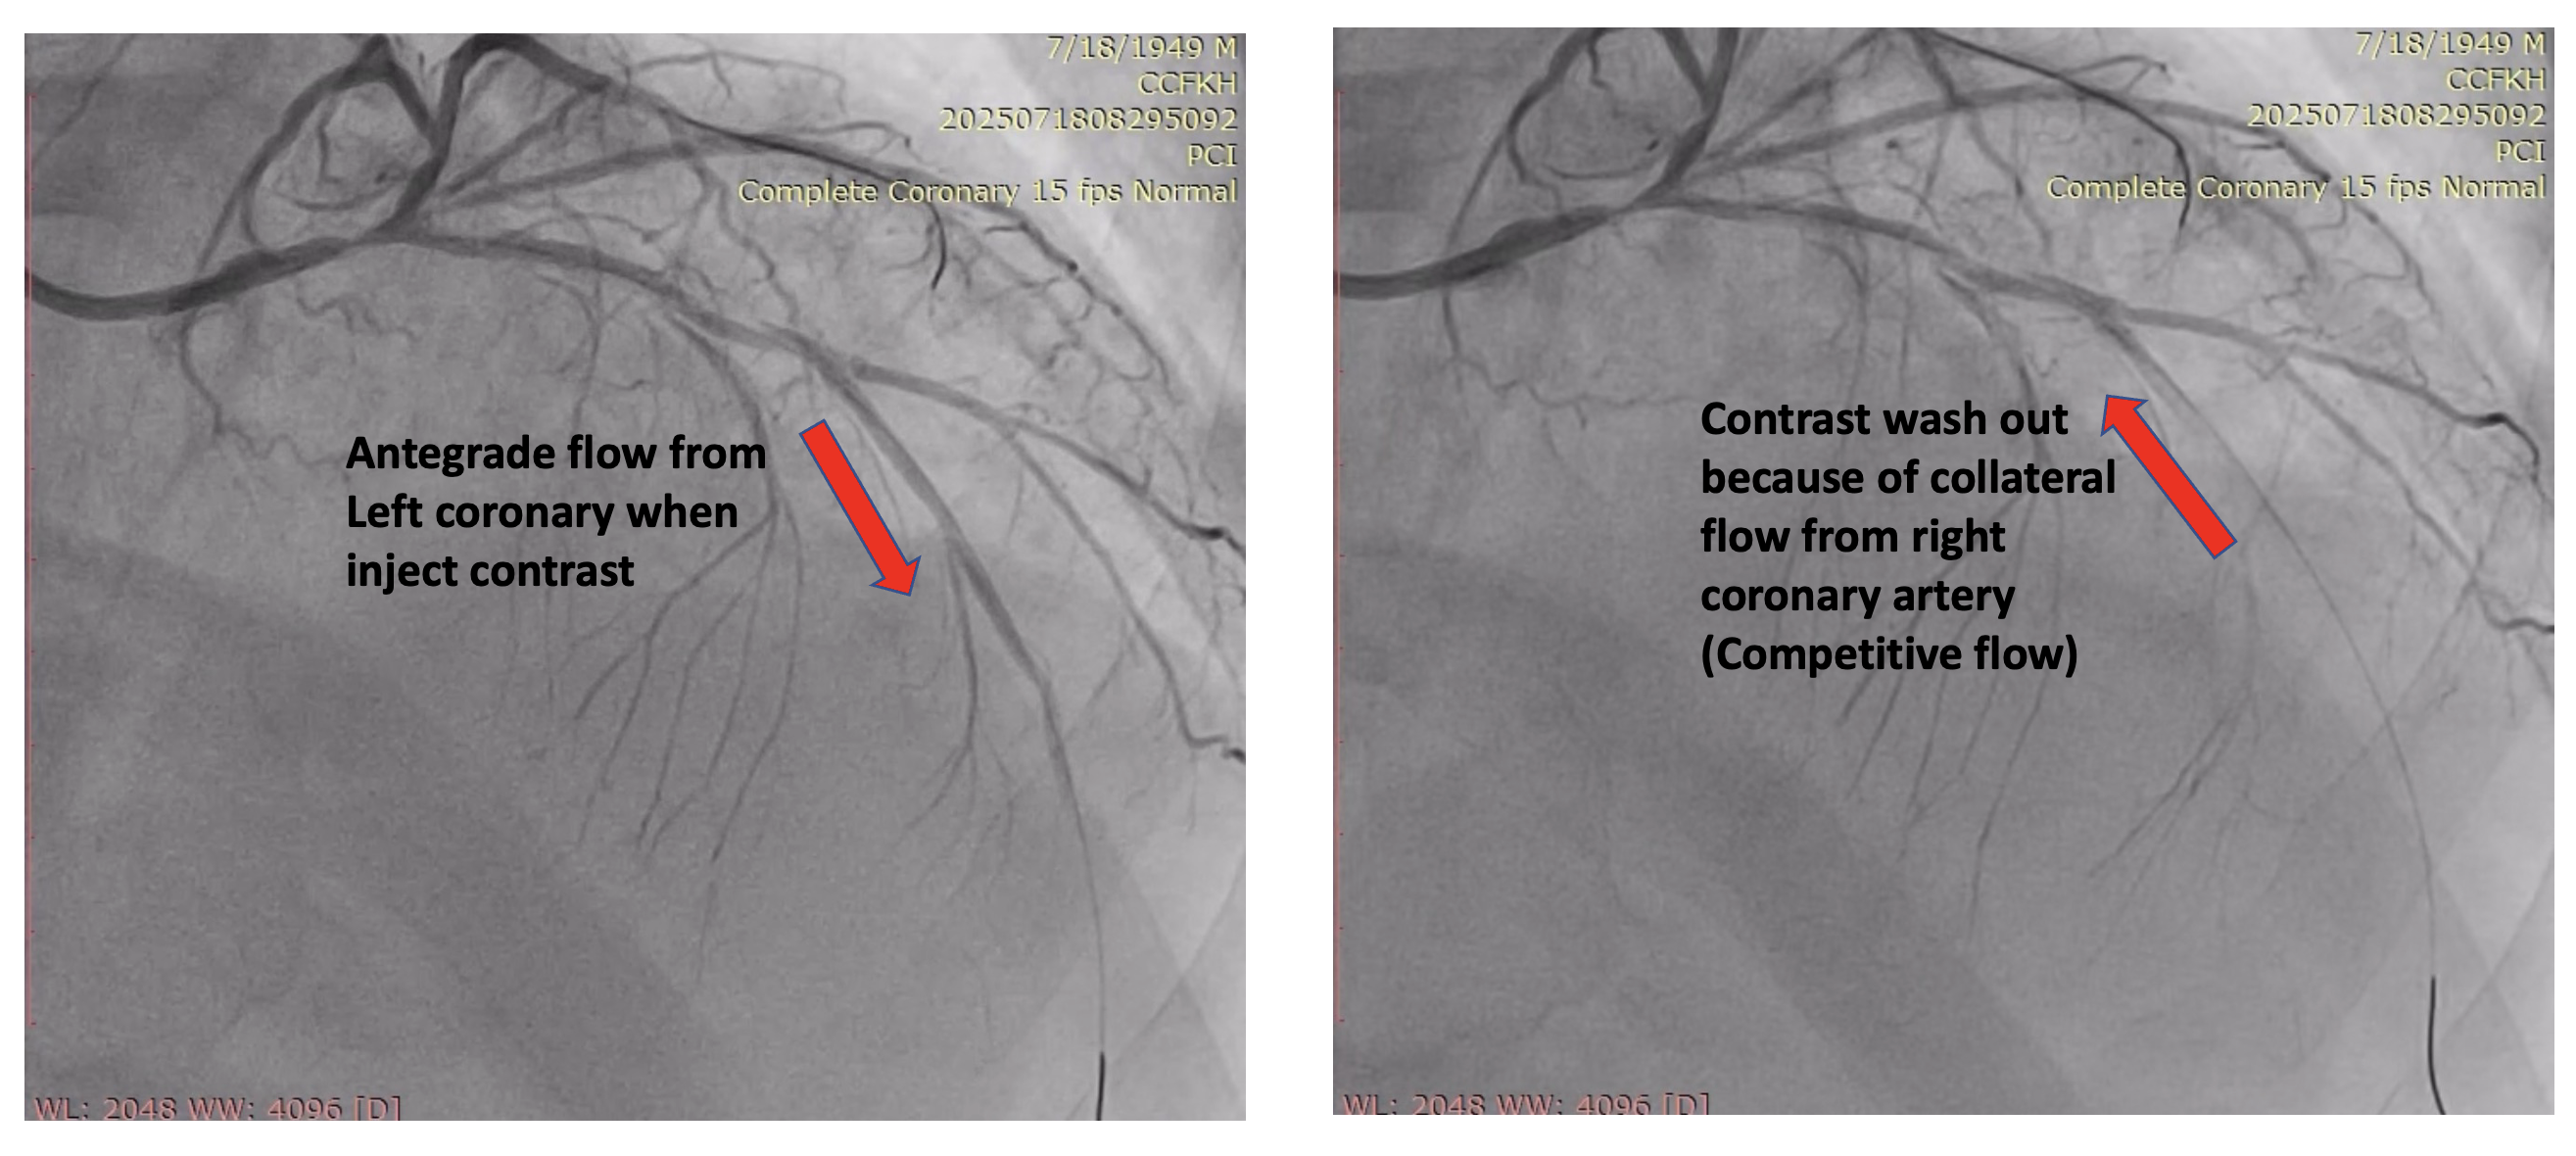

The left main was engaged by 6F EBU 3.5 via radial sheath. The LM occlusion was crossed by using workhorse guidewire (Cougar XT), suggesting an acute occlusion. Predilation with SC balloon (Sprinter Legend 1.5 x 12mm and Sprinter Legend 2.5 x 12mm) was performed at the occlusion site, resulting an antegrade flow from LM, but there was still no flow distally from mid-LAD.Plain old balloon angioplasty by Sprinter Legend 2.5 x 12mm performed at the mid-LAD, the flow from mid-LAD still was not achieved, giving the hypothesis of no reflow phenomenon. IC Nitroglycerine 100ug and IC Nicardipine 100ug were given several times, resulting a vasodilation and a better flow. It therefore revealed a significant competitive flow from powerful collaterals from the right coronary artery, ruling out the no reflow hypothesis (Refer to videos below for better illustration). Onyx Trucor DES 2.75 x 34mm, Onyx Trucor DES 3.0 x 22mm, and Onyx Trucor DES 3.5 x 22mm were implanted respectively from distal LAD to LM, and restored final TIMI 3 flow result

Case Summary